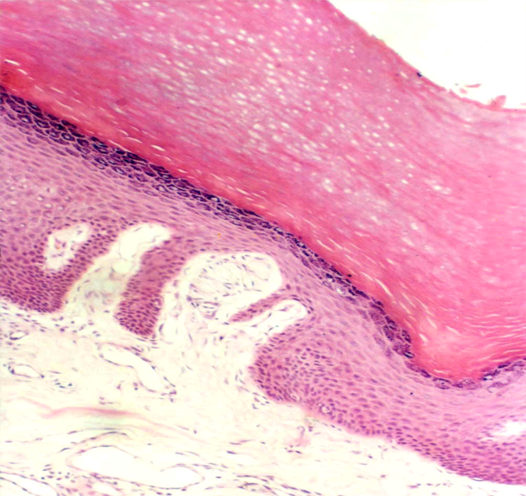

5.复层扁平上皮stratified squamous epithelium 由多层细胞组成,因表层细胞呈鳞状,又名复层鳞状上皮。由垂直切面看,细胞的形状不等。紧贴基膜的一层细胞立方形或矮柱状,为有增殖、分化能力的干细胞,其产生的部分细胞向层移动;基底层以上是数层多边形细胞,再上为梭形细胞,浅层为几层扁平细胞最表层扁平细胞已退化,不断脱落。上皮与深部结缔组织的连接面凹凸不平,扩大了两者的连接面,既保证上皮的营养供给,又使连接更加牢固(图2-5)

位于皮肤表面的复层扁平上皮,浅层细胞核消失,胞质中充满角蛋白(一种硬蛋白),是干硬的死细胞,有更强的保护作用,称角化的复层扁平上皮。衬贴在口腔和食管等腔面的复层扁平上皮,浅层细胞是有核的活细胞,含角蛋白少,称未角化的复层扁平上皮。复层扁平上皮有很强的机械保护作用,耐摩擦和阻止异物侵入等作用。受损伤后,上皮有很强的修复能力。

图2-5A 复层扁皮上皮模式图

图2-5B 食管腔面未角化的复层扁皮上皮  图2-5C 皮肤表面角化的复层扁皮上皮

图2-5 复层扁皮上皮